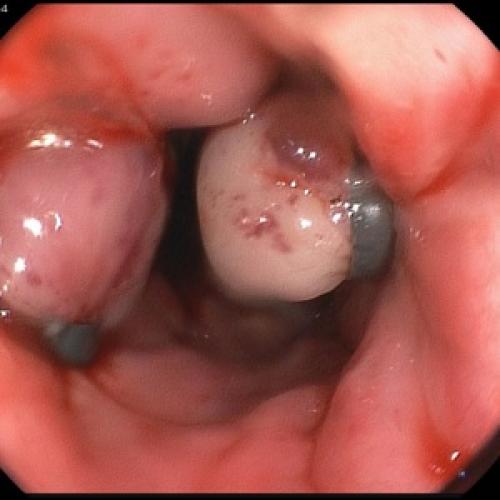

Гастроскопия

Гастроскопия при панкреатите даёт возможность оценить вовлечённость в патологический процесс желудка и двенадцатиперстной кишки. В некоторых случаях с помощью гастроскопии можно установить, что спровоцировало развитие острого воспаления.

Пациентам с предположительным клиническим диагнозом острого панкреатита показано выполнение ЭГДС (дифференциальный диагноз с язвенным поражением гастродуоденальной зоны, осмотр БДС).

Отсутствие эффекта от проводимой анальгетической и спазмолитической терапии в течение 12-48 часов, быстро прогрессирующая желтуха, отсутствие желчи в ДПК при ЭГДС, признаки билиарной гипертензии по данным УЗИ свидетельствуют о стеноза терминального отдела холедоха (вклиненный конкремент БДС, папиллит). В этом случае показано проведение ЭПСТ. При остром панкреатите ЭПСТ производится без ЭРХПГ!